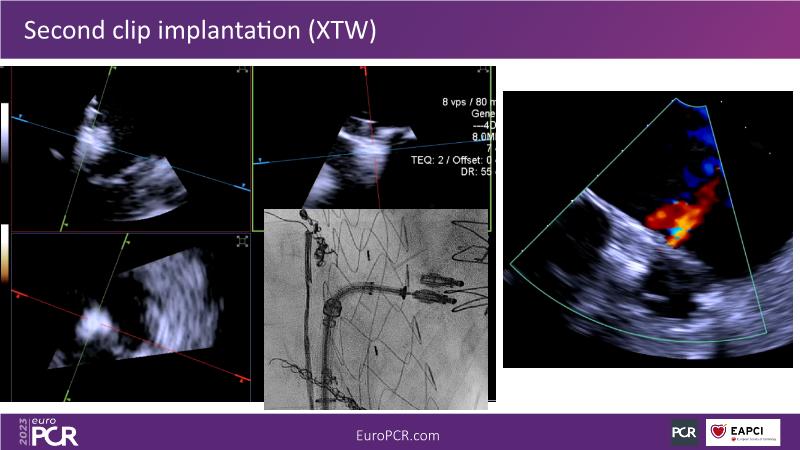

Use of 4D ICE in tricuspid and mitral valve interventions

Watch this session to know the challenges of TV imaging, to get an overview on 4D ICE technology, and to study both a transcatheter tricuspid valve procedure and a transcatheter mitral valve procedure through different case presentations, that will then be discussed.

- To get familiar with the 4D ICE technology and how it can support the imaging and guidance in complex structural heart disease interventions

- To understand the use of 4D ICE and benefits in tricuspid and mitral valve interventions